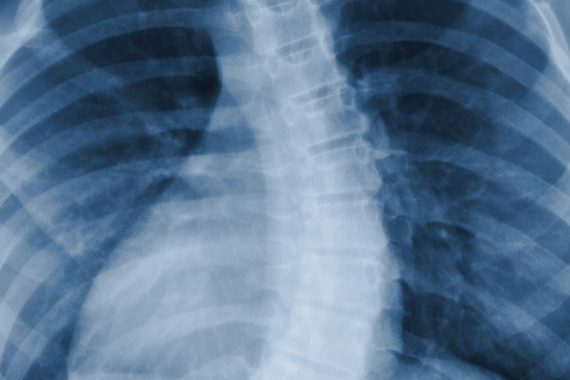

Before planning children and adolescents Scoliosis strength exercises program in Antalya Medworld Clinic, Turkey, doctors utilize CT scan, MRI, spinal radiograph and x-ray machines to diagnose scoliosis. If the posterior and anterior radiograph shows more than 10 degrees of a curvature of coronal, scoliosis diagnosis is positive. When the degree is more than 25, more distinct scoliosis is on the table. On the other hand, more than 45 degrees of curvature means severe scoliosis, which requires surgery or heavy physical therapy and rehabilitation.

X-ray

Doctors take X-ray images to see any infections, malfunctions, or fractures that might be the underlying reasons for scoliosis because it provides an image of joints and vertebrae structure.